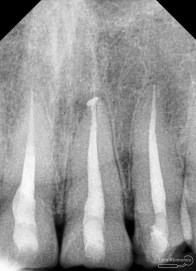

dan ini foto ronsen nya…

Dari pemeriksaan radiografis lokasi fraktur menyerempet kamar pulpa pada ketiga gigi tersebut… Saya sampaikan kepada pasien bahwa ketiga gigi tersebut memerlukan perawatan saluran akar terlebih dahulu baru kemudian dilanjutkan dengan restorasi indirek… kenapa saya pilih restorasi indirek? Pertimbangannya adalah sisa struktur mahkota gigi yang ada bila hanya di “sambung” dengan restorasi direk dalam jangka panjang rentan mengalami kerusakan, yang kedua pemilihan warna akan lebih maksimal pada kasus ini…. Pasien setuju dengan rencan perawatan yang saya jelaskan…

Nah dari foto ronsen ini juga saya melakukan evaluasi hasil pengisian pada gigi 11 21 nya… alhamdulillah pengisian yang kemarin terlihat sepanjang kerja dan padat serta rapat… Pada gigi 22 nya pun pengepasan guttap terlihat sudah sepanjang kerja…

Dari foto ronsen terlihat gambaran yang “indah” dari mulai pengisian saluran akar yang rapat dan padat serta gambaran sementasi mahkota yang terlihat homogen….